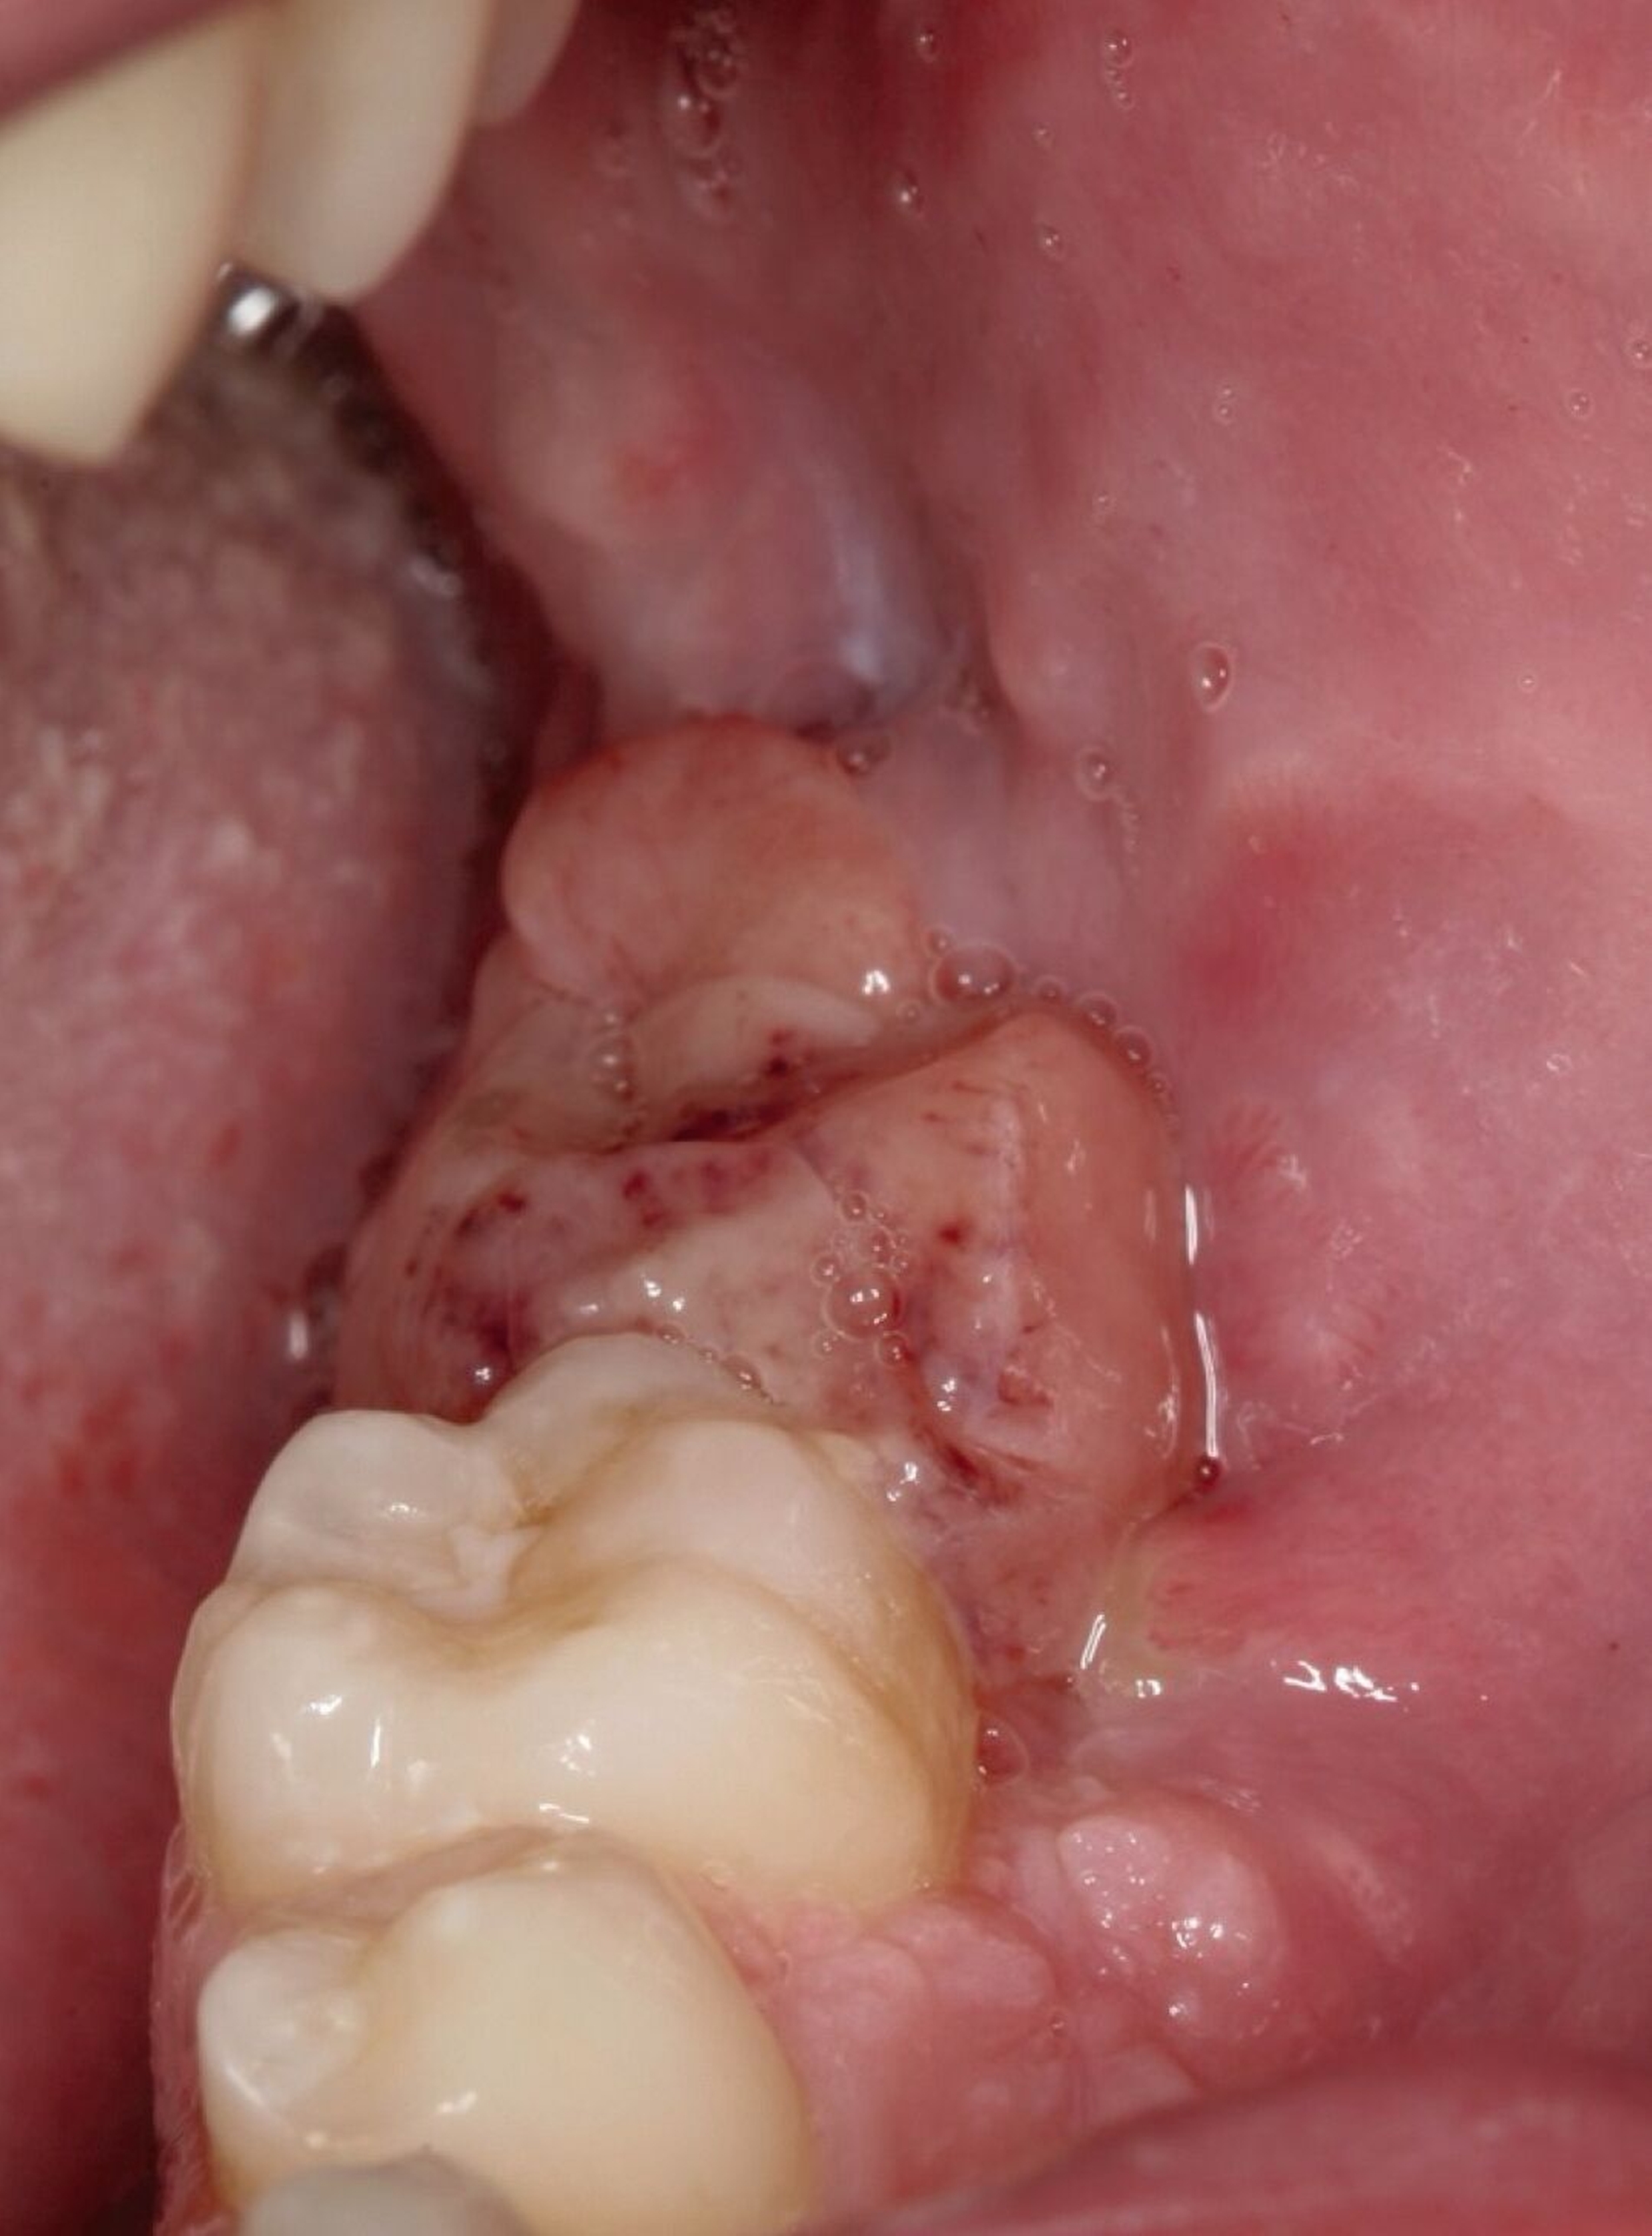

Bei Verdacht auf das Vorliegen einer Keratozyste und zum Ausschluss eines Malignoms wurde die chirurgische Entfernung der Befunde in Intubationsnarkose durchgeführt. Hierbei erfolgte die Zystektomie beider Raumforderungen gemeinsam mit der Osteotomie der Zähne 37, 38, 47 und 48. Insbesondere in regio 38 zeigte der Befund eine direkte Kontinuität zwischen Knochen und Weichgewebe. Das Resektat wies eine gelbliche Farbe und eher weiche Konsistenz auf (Abbildung 4).

In Anbetracht der doch beträchtlichen Größe der Wundhöhle wurde diese anschließend mit Beckenkammspongiosa aufgefüllt. In der anschließenden histopathologischen Aufarbeitung kam eine fragmentierte spindelzellige und riesenzellhaltige Läsion des Weichgewebes mit lokal den Knochen destruierendem Wachstumsverhalten zur Darstellung. Zudem zeigte der Befund starke Entzündungszeichen, was die differenzialdiagnostische Beurteilung deutlich erschwerte. Zur Klärung der Dignität des Befunds wurde dieser zur referenzpathologischen Mitbeurteilung versandt. Auch in dieser wurde ein polypoides, teils plattenepithelial überkleidetes Exzidat mit ausgedehnter Ulzeration sowie einem kapillarreichen Granulationsgewebe mit diffus verteilten Riesenzellen beschrieben (Abbildung 5). In beiden pathologischen Berichten wurde die Raumforderung als primär mit einem Riesenzellgranulom vereinbar erachtet.